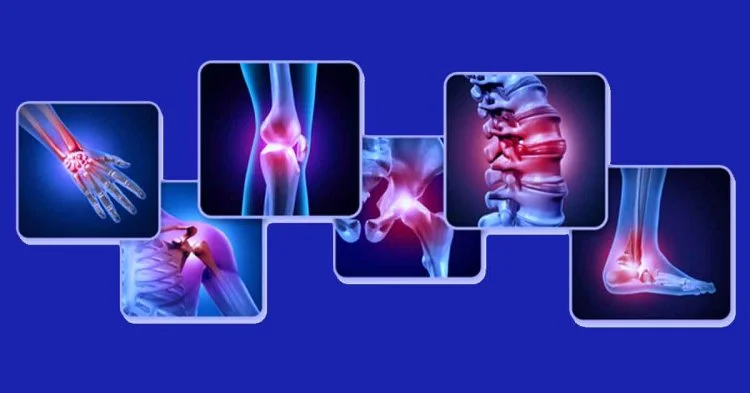

At Ekanshi Multispecialist Hospital, we provide expert Orthopedic Treatment in Handewadi, Hadapsar, also known as bone and joint care, to help patients restore mobility and live pain-free lives. The musculoskeletal system includes bones, joints, muscles, ligaments, and tendons that support movement and maintain body stability. Orthopedic conditions can develop gradually, such as arthritis and degenerative joint disease, or suddenly due to fractures, ligament tears, sports injuries, or accidents, often caused by aging, trauma, repetitive strain, or osteoporosis. As a result, patients may experience persistent joint pain, swelling, stiffness, reduced range of motion, difficulty walking, muscle weakness, or deformity, affecting their daily activities and overall quality of life.

Orthopedic conditions can affect bones, joints, muscles, ligaments, and the spine. Symptoms may develop gradually due to wear and tear or suddenly due to injury. Common signs include:

Orthopedic conditions can develop due to injuries, age-related wear and tear, underlying medical conditions, or lifestyle factors that affect bones, joints, muscles, and the spine. The most common causes include: